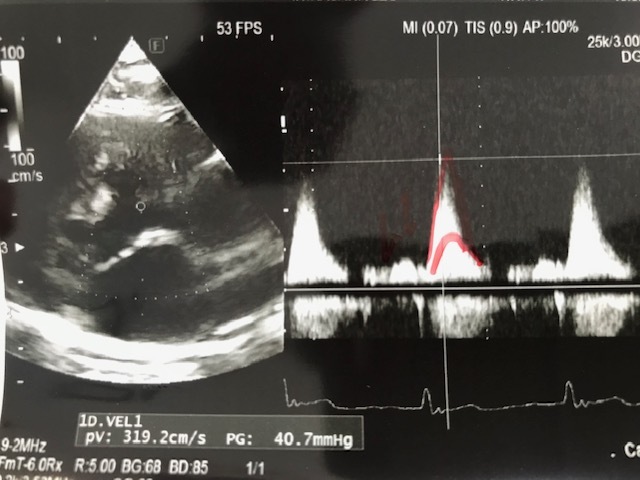

心臓の超音波検査:

三カ月前と比べて大きな変化がないとの事。